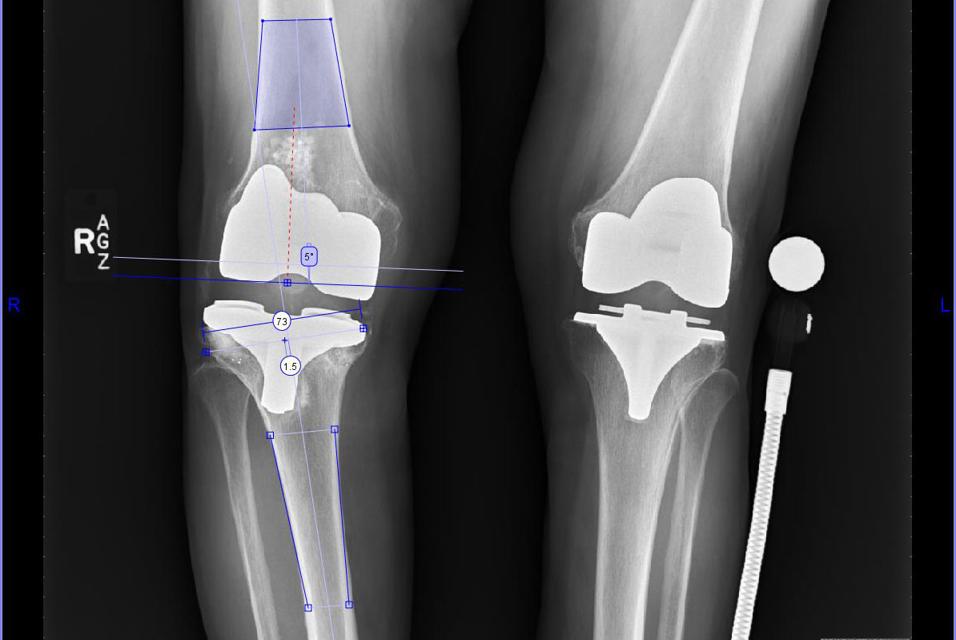

- It was identified that stemmed components were required for both the tibia and the femur.

- We determined that a tibial augment was required as a result of the varus failure of the tibial component and medial tibial bone loss.

- The offset value provided by the software identified that an offset tibial component was required to avoid an abutment of the cortex by the tibial stem.

Joint line:

- We were able to assess how the preoperative plan would affect the joint line and determined that it would maintain it reasonably well.

In revision cases, the existing femoral and tibial component positions are ignored, and bony landmarks are used to identify where to place the femoral and tibial preoperative planning tools.

The preoperative planning software allows the width of the femur and tibia to be assessed for proper component sizing, which is important as size is the primary focus, rather than angles. Intramedullary guides are used to restore the mechanical axis. Also key with revisions is identifying where the articular surfaces of the revision components would lie, in relation to the shaft. Further, it is helpful to preoperatively determine the offset of the tibial component (more than that of the femoral component), as this can help intra-operatively reduce the need for trialing of various tibial stems.

The tibial AP axis indicates that an offset tibial stem will be needed.